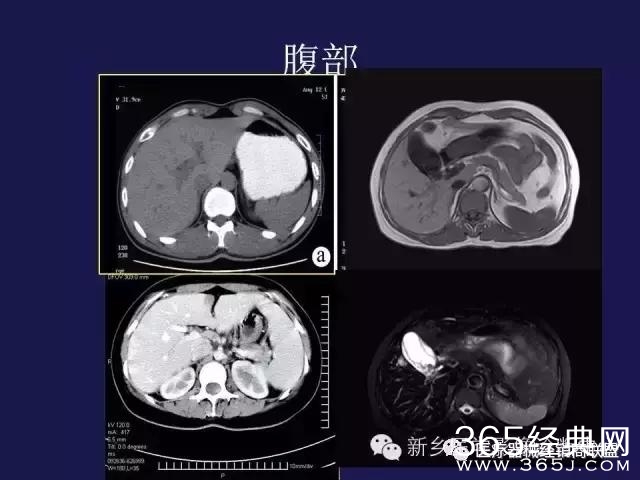

CT、MRI很难?NO,今日我们一起来学习一下如何读CT、MRI!

内行看门道:

整整90张图